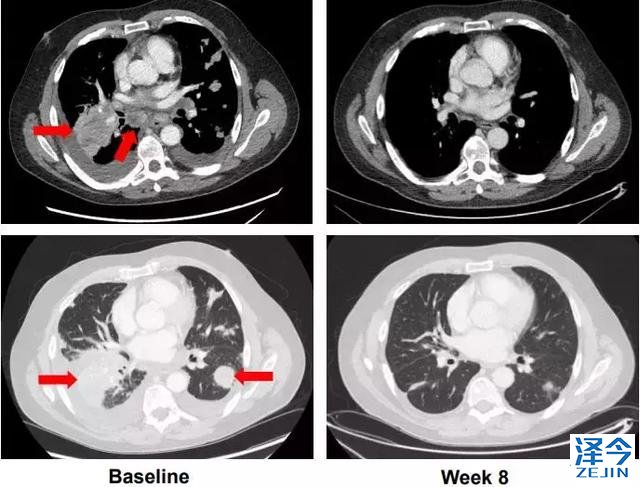

61岁男性转移性低分化甲状腺癌;NCOA4-RET融合阳性

在lenvatinib后出现进展,并有呼吸急促,胸痛的症状,LOXO-292治疗八周后评估,最大肿瘤减少-72%,并且患者的症状全部消失,已经重回工作岗位。